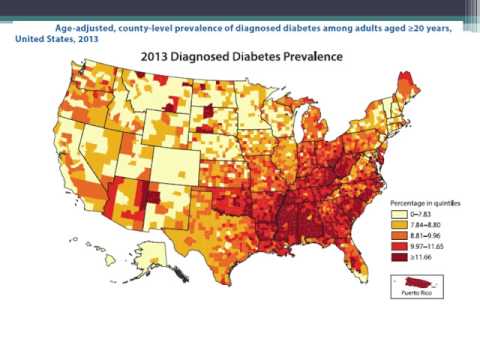

Diabetes en los EEUU. Dra. María Laura Estrella. Residencia de Cardiología. Hospital C. Argerich. Buenos Aires